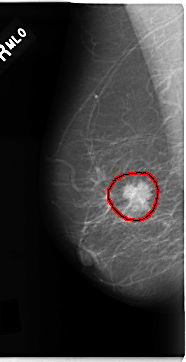

C_0181_1.RIGHT_CC

FILE: C_0181_1.RIGHT_CC.OVERLAY

TOTAL_ABNORMALITIES 1

ABNORMALITY 1

LESION_TYPE MASS SHAPE IRREGULAR MARGINS SPICULATED

ASSESSMENT 5

SUBTLETY 5

PATHOLOGY MALIGNANT

TOTAL_OUTLINES 1

BOUNDARY